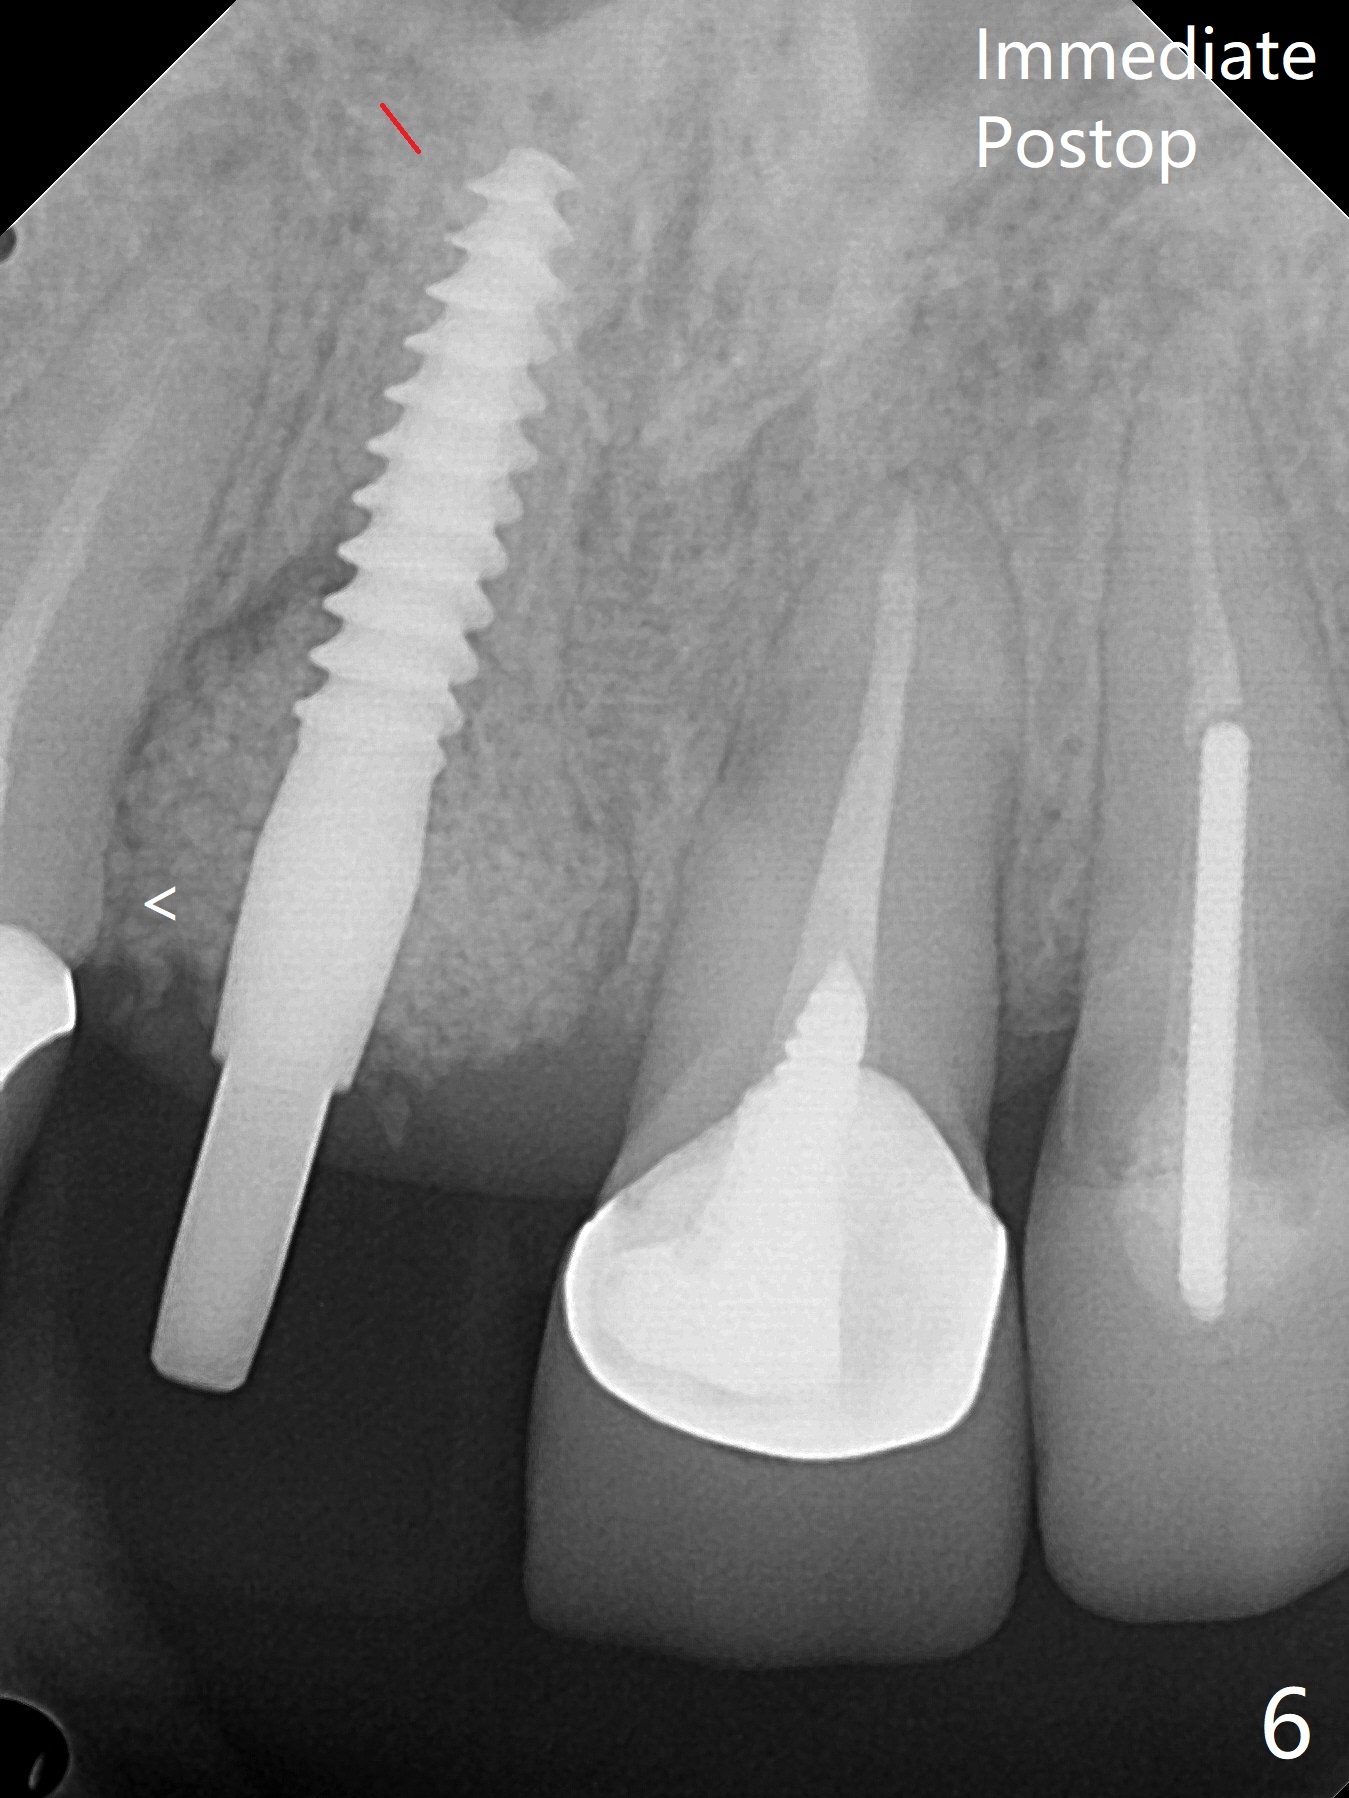

徒手初步钻洞显示方位不对(图一),重新钻洞方位尚可,好像接近鼻底(图二:红线);植入3x11.5毫米一段式植体(图三),3-5个螺纹暴露,植体似乎接近鼻底;旋转植体三趟,植体仿佛卡人鼻底,扭力大约35Ncm,植入粘性骨粉(图四,五:*)前,塞入PRF膜,紧贴颊侧粘膜,促进瘘道愈合。骨粉不仅围绕植体,而且紧贴邻牙牙根(图六(第二轮植骨:overgrafting):<)。病人术后第二周开始使用水牙线,术后三周牙龈健康多了,瘘道消失(图七)。术后六周颊侧骨壁开始塌陷(图八:>),临时牙冠颊侧颈部显得隆起(*)。调整后,牙冠外形改善(图十一至十三),取模前颊侧牙龈缘有可能下降,两个中切牙龈缘可能一致。术后3.5个月骨粉形态(图十四)与术后即刻(图六)有所不同。颊侧牙龈仍红肿轻度触痛(图十五),可能因为临时牙冠不利于局部卫生,所以决定取模制作永久性牙冠。粘固时使用临时胶水,并且涂抗菌素。另外一个可能因素是颊侧骨板薄(图十六:*),细菌感染植体螺纹,永久性牙冠粘固前,拍摄CT(放置cotton roll),必要时,植骨。永久性牙冠远中有缝隙,为了预防病人后悔,使用临时性粘固剂固定(图十七)。Return to No Caries DIO 下一个病例 一段式植体边缘制备 导板与内提升 Xin Wei, DDS, PhD, MS 1st edition 12/22/2020, last revision 06/15/2021